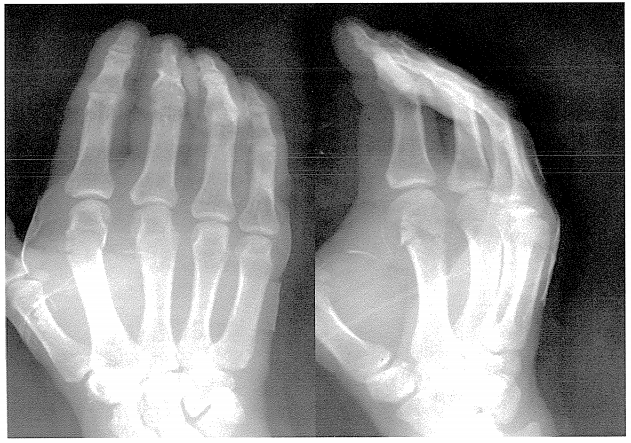

問題223

31歳の男性。空手の稽古中、試し割りで板を拳で突いた際に受傷した。第2MP関節付近に強い疼痛と腫脹を認め、拳を握ると疼痛が増強する。単純エックス線写真(別冊No.3)を別に示す。この疾患で適切でないのはどれか。

1. 転位には骨間筋と虫様筋が作用する。

2. 側副靭帯を弛緩させると整復が容易になる。

3. 屈曲変形が残存すると伸展障害を起こす。

4. オーバーラッピングフィンガーに注意する。

答え.2